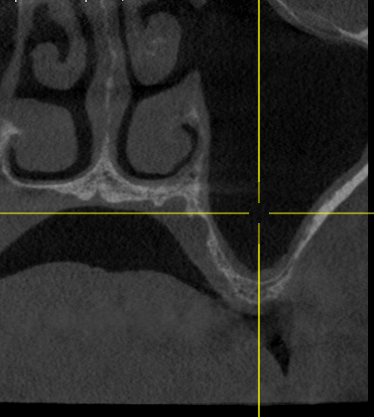

Пациент обратился с целью протезирования. На компьютерной томографии выявлен недостаток костной ткани по высоте (3−5 мм) за счет углубления гайморовой пазухи. Следующим этапом в области отсутствующих зубов 1.5, 1.6 и 1.7 планируется дентальная имплантация.

Врачом А.Г. Геворкяном выполнена операция по наращиванию костной ткани (открытый синуслифтинг). На контрольном снимке определяется увеличение объема костной ткани по высоте.